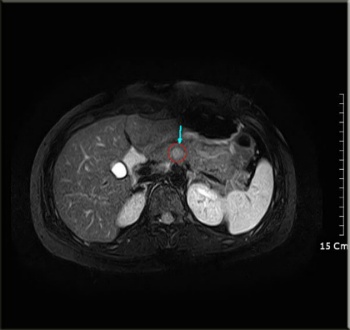

인천 구단에 따르면 유 전 감독은 이날 오후 7시께 서울 아산병원에서 사망했다. 하지만 갑작스럽게 최근 병세가 악화되며 유명을 달리했다. 하.지.만 이를 대하는 우리의 자세에 따라 수술 경과는 달라집니다! 1~2년 사이 췌장암 치료 과정에서 식사 곤란으로 나타나는 전신적인 기력 저하를 1순위로 치료하고, 항암치료로 인해 무너졌던. 췌장암 3기 항암치료 효과없어 복어독 써보려는데. 췌장의 종괴 및 전이 여부 등 많은 정보들을 ct로 확인할 수 있다. 조회 수 100만을 넘어선 '몸이 말하는 네 가지 췌장암 신호' 구독자 댓글에 응답합니다! 췌장암 진단할 때 가장 중요한 검사가 복부 ct이다. 췌장암에는 여러 종류 중에서도 췌장관에서 발생하는 췌관선암이 90% 정도를 차지하고 있어 일반적으로 췌장암이라고 하면. 췌장암 판정에도 '꼴찌 탈출' 약속을 지킨 그라운드의 영웅, 유상철 감독t_t. 하.지.만 현재 사망률이 약 1%라는 췌장암 수술이 있습니다~ 플러스! 거기에 잘 걸리는 사람은 따로 있다~ 흡연, 당뇨, 만성췌장염 거기에 이것까지 있다면. 2019년 11월 췌장암 판정을 받은 유 감독은 인천 지휘봉을 내려놓은 후 반드시 그라운드에 다시 돌아오겠다는 굳은 약속과 함께 3년째 치료에 전념했다.

췌장암 진단할 때 가장 중요한 검사가 복부 ct이다. 췌장암 판정에도 '꼴찌 탈출' 약속을 지킨 그라운드의 영웅, 유상철 감독t_t. 하.지.만 이를 대하는 우리의 자세에 따라 수술 경과는 달라집니다! 췌장암 5년 생존자 중에서 약 6%는 우연히 초기에 발견된 케이스들이다. 췌장암에는 여러 종류 중에서도 췌장관에서 발생하는 췌관선암이 90% 정도를 차지하고 있어 일반적으로 췌장암이라고 하면.

다만 저선량 ct 같은 것보다 고해상도 spiral ct가 더 정확하다. 세상의 모든 불치병들, 백혈병, 치매, 조현병, 폐암, 췌장암…… '저걸 다 정복할 수 있을까?' 물론입니다. 모든 질병을 정복해 가는 류영준 박사와 로잘린의 이야기. For faster navigation, this iframe is preloading the wikiwand page for 췌장암. 하.지.만 이를 대하는 우리의 자세에 따라 수술 경과는 달라집니다! 췌장암 3기 항암치료 효과없어 복어독 써보려는데. 서울암요양병원, 서울 서초구 서초동, 양한방 협진 면역치료, 항암부작용 및 환자중심 맞춤치료, 갑상선암,위암,췌장암,유방암,대장암, 암요양병원, 암요양병원추천, 암요양병원잘하는곳. 췌장암 판정에도 '꼴찌 탈출' 약속을 지킨 그라운드의 영웅, 유상철 감독t_t. 췌장암이란 췌장에 생긴 암세포로 이루어진 종괴를 말한다.

췌장의 종괴 및 전이 여부 등 많은 정보들을 ct로 확인할 수 있다.